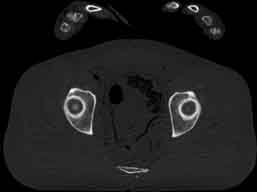

Visible Human male: Sectio transversalis 1857

CT

NMR

Pd                          / T2 \                         T1